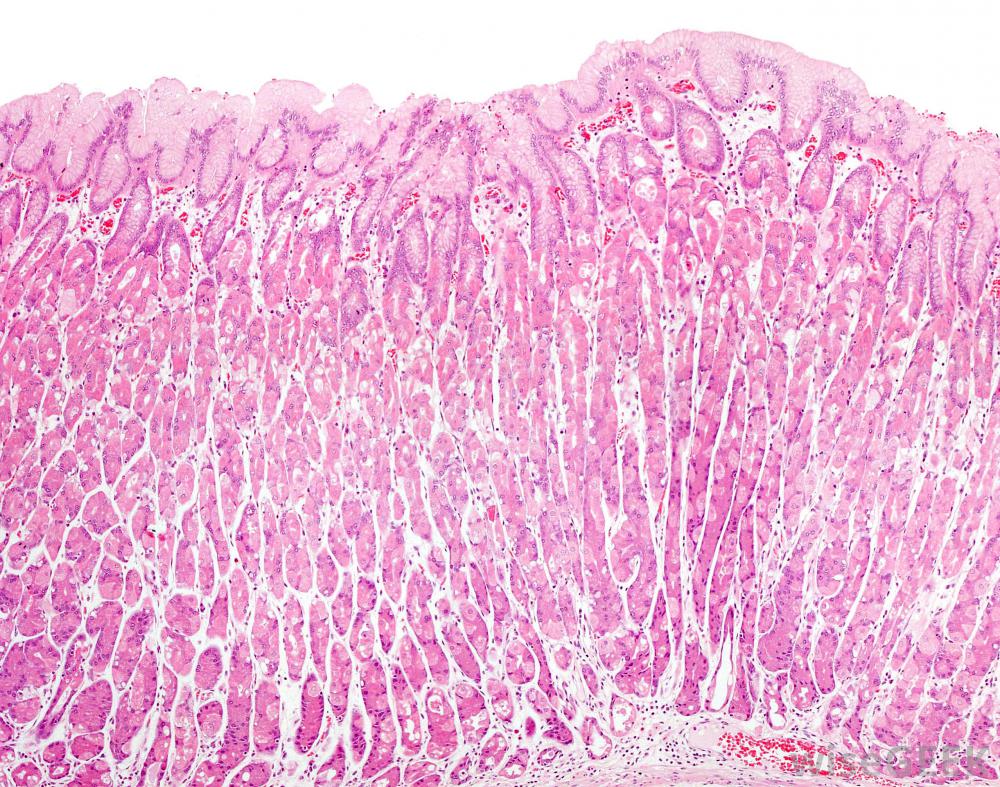

Pepzingi®用于治疗胃部不适。与其他治疗胃和消化问题的方法不同,Pepzingi®不会中断消化过程,例如产酸。相反,肌肽锌支持人体的自然黏膜防御系统,以防止感染并促进愈合。Pepzingi®被认为覆盖并粘附在胃壁上,为保护胃粘膜免受胃壁的影响提供保护消化酸。

胃壁细胞产生粘液,保护胃免受酸侵蚀。美国食品和药物管理局(FDA)承认2002年确认了Pepzingi®的新膳食成分状况一种新的膳食成分是1994年以前在美国没有作为膳食补充剂出售的成分。制造商如果想销售含有这种成分的产品,必须通知食品和药物管理局,并附上文件,说明如果按照标签上的推荐用途和剂量食用,这种补充剂是安全的自1992年提交给FDA以来,对Pepzingi®进行了多个随机和安慰剂对照临床试验和研究。在一项此类研究中,299名胃部不适和不适的患者随机服用安慰剂或Pepzingi®。在139名服用Pepzingi®的受试者中,92%的受试者服用了Pepzingi®据报道,症状得到了适度改善或好转。除了缓解胃不适和溃疡外,这种补充剂还有其他潜在的临床用途。研究人员已经探索了它作为骨质疏松症、肝炎、胰腺炎的治疗方法,肌营养不良和各种味觉和嗅觉障碍。它也可能是锌缺乏症的有效治疗方法。在2010年完成的任何临床试验和研究中,Pepzingi®没有任何严重的副作用。它与任何处方药或其他膳食补充剂没有任何已知的相互作用在开始服用这种补充剂之前,应咨询医生,以避免任何不可预见的并发症。